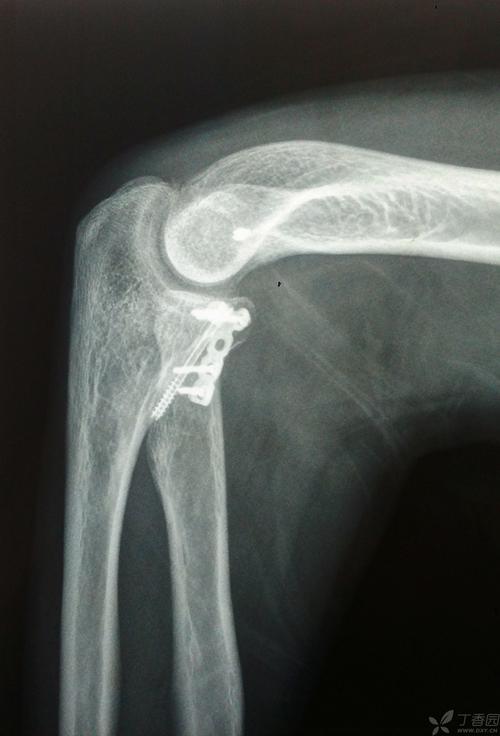

桡骨近端骨折,桡骨小头骨折图片

桡骨近端骨折分型

注册x 尺骨近端骨折术后第一天复查的片子.术前桡骨头无脱位.